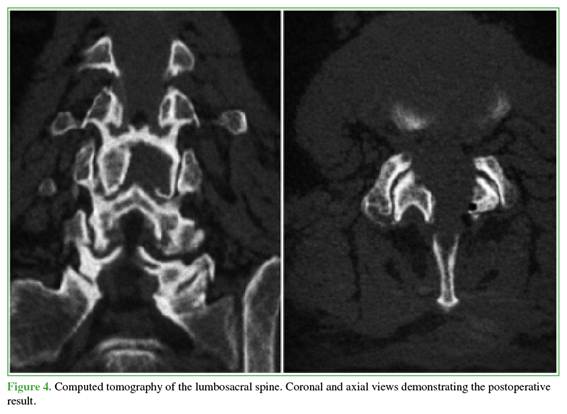

The findings were consistent with a hemorrhagic juxtafacet synovial cyst. Given the acute presentation with progressive motor neurological deficit and severe radicular compression, the patient underwent urgent decompression. The objective was to relieve neural compression, reverse the motor deficit, and allow rapid functional recovery while minimizing invasiveness. A posterior interlaminar uniportal endoscopic decompression was performed using a contralateral (left-sided) approach and the “over-the-top” technique (above the dural sac) to achieve safe and complete cyst resection (Figures 2-5).

The patient had a favorable immediate postoperative course. Within the first 24 hours, pain improved markedly (2/10 on the visual analog scale), and motor recovery was incipient. He was discharged 24 hours after surgery with an outpatient physical therapy program. At the 7-day follow-up, ankle dorsiflexion strength had improved to 5/5.